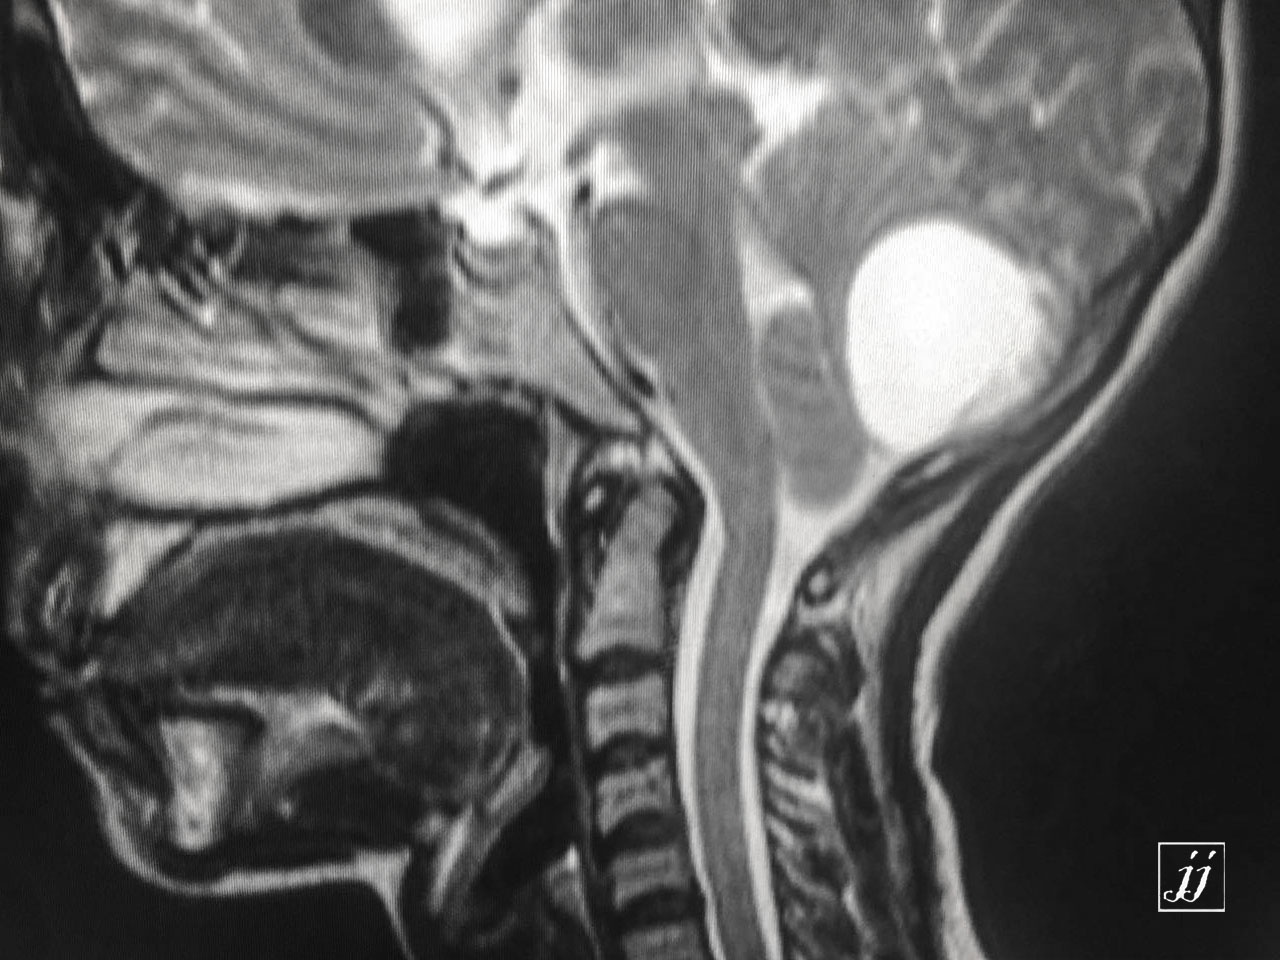

Brain- mega cisterna magna (5)